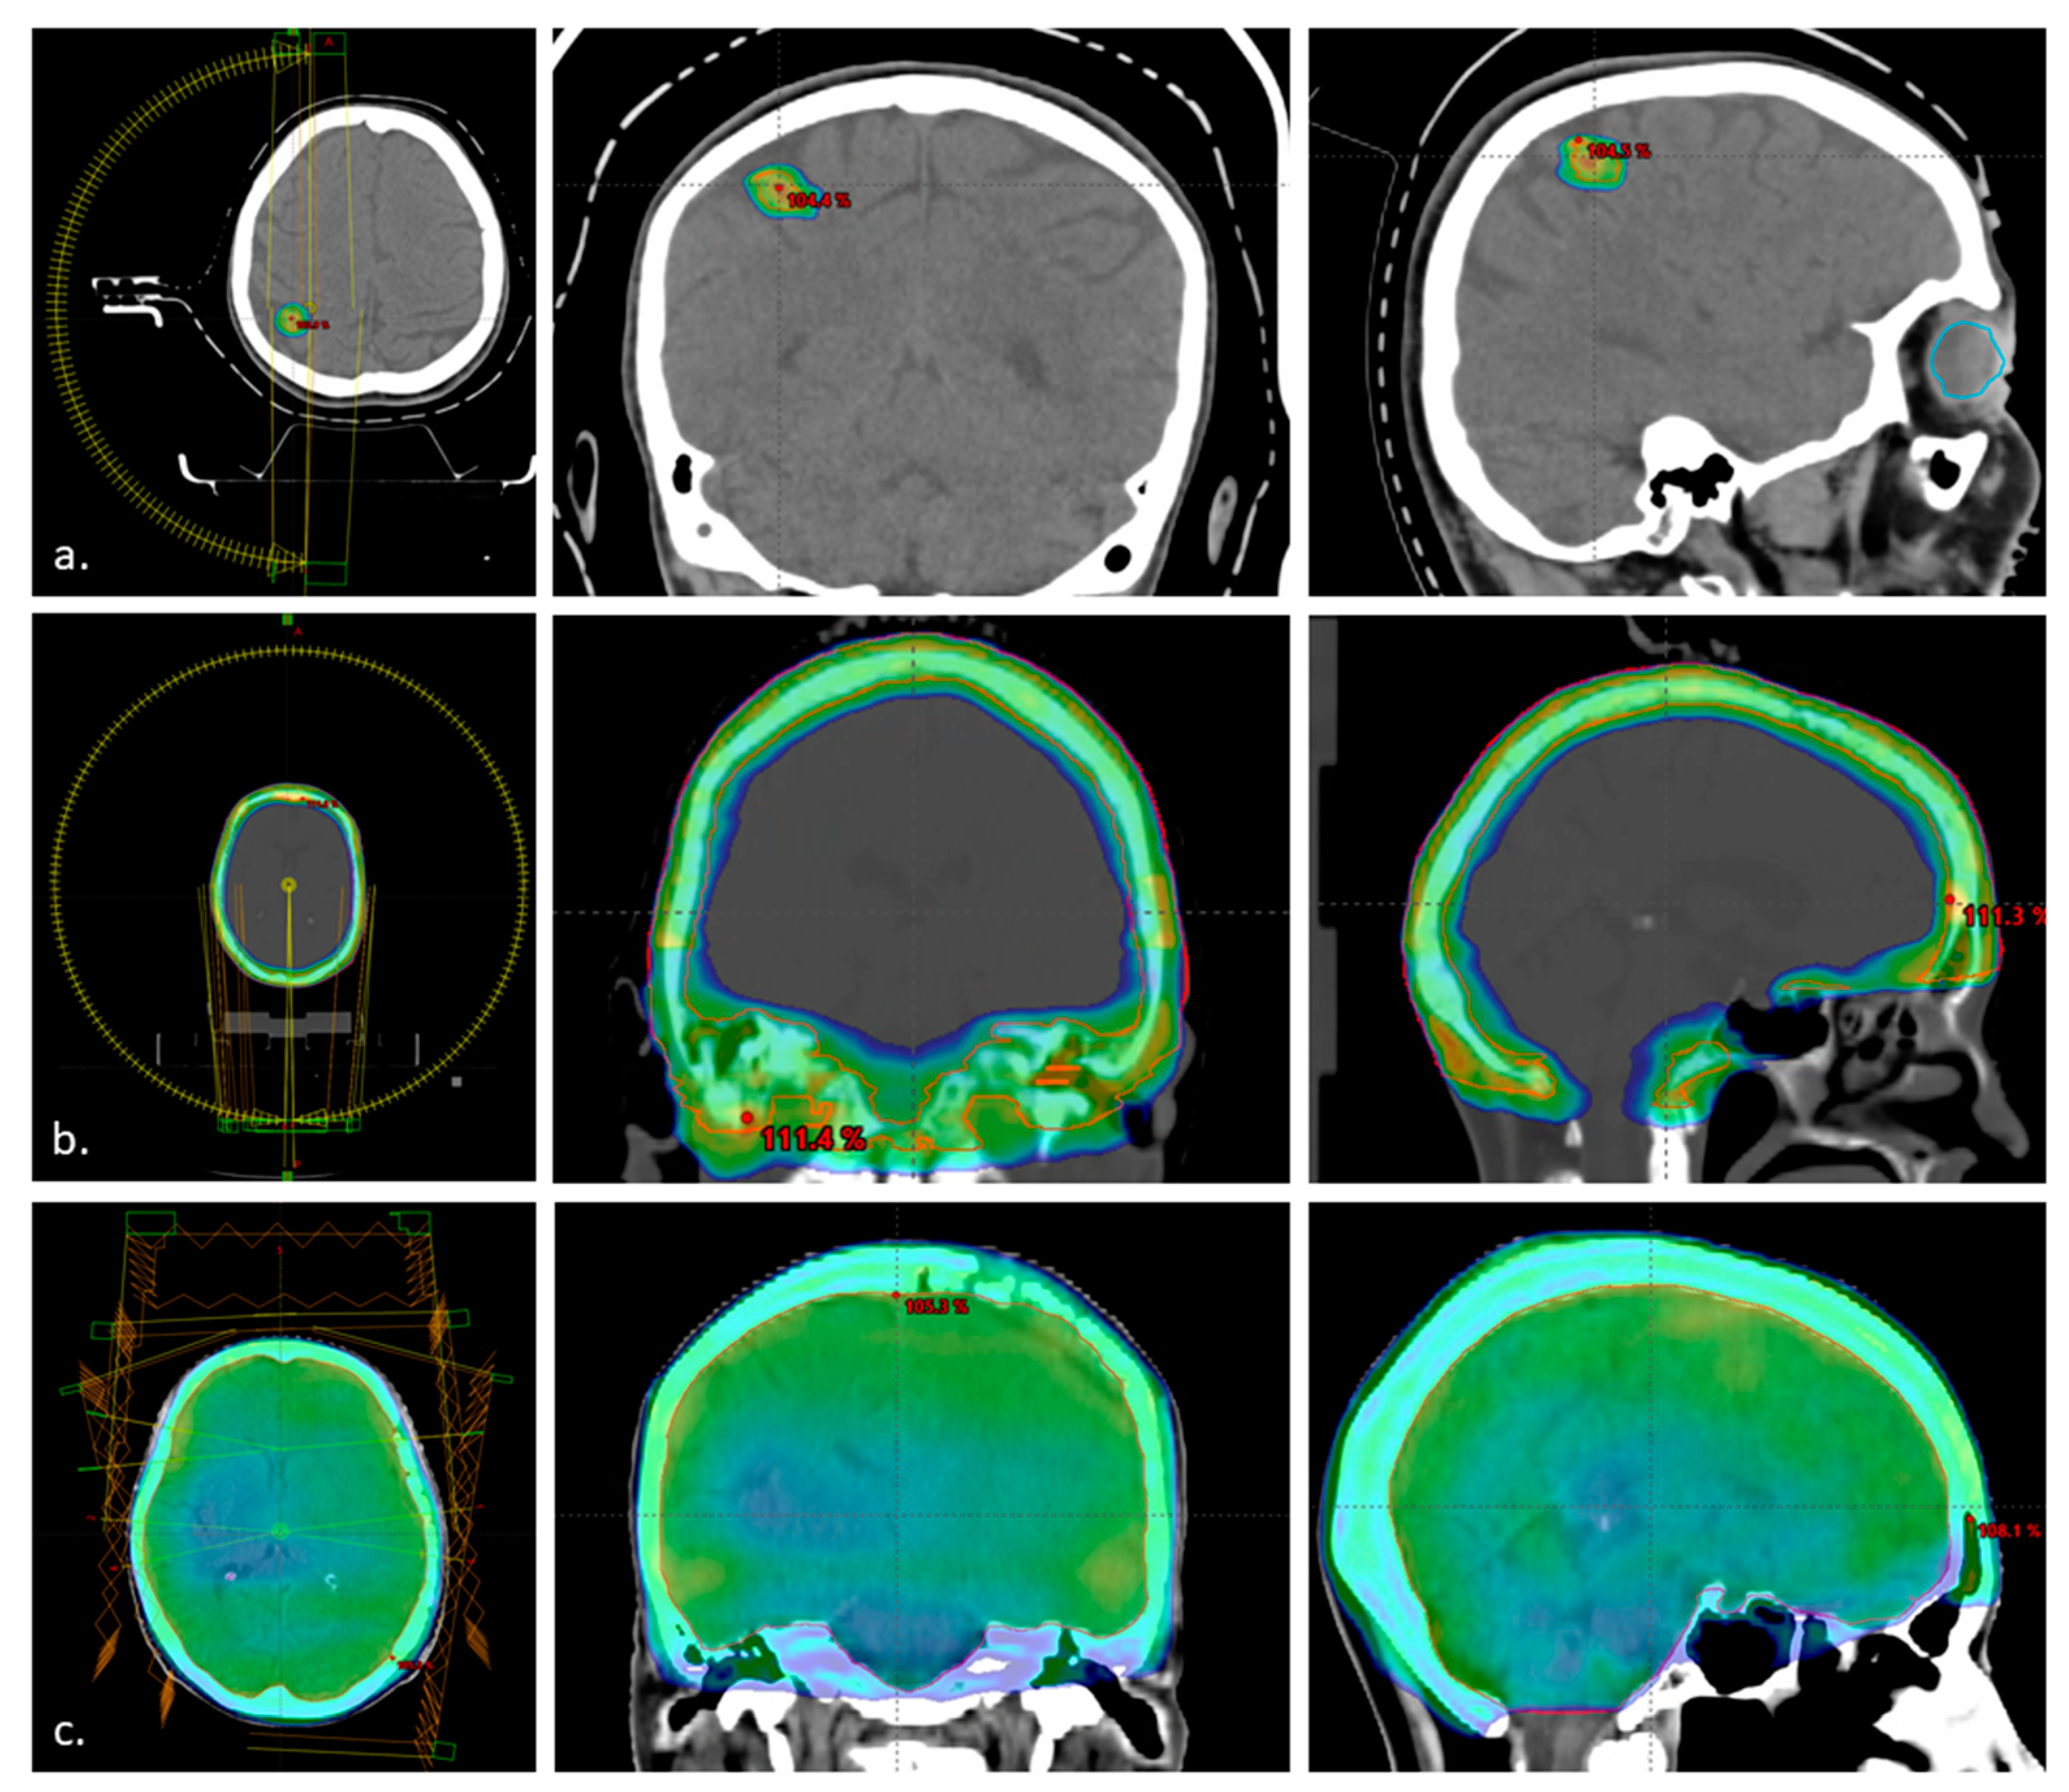

| Technique | RT Total Dose (Gy) | RT Dose per Fraction (Gy) | No. of pts n = 24 (%) |

|---|---|---|---|

| GammaKnife | 20 | 20 | 1 (4%) |

| CyberKnife | 15 | 5 | 1 (4%) |

| Linac Stereotactic Radiation Therapy | 24 | 8 | 2 (8%) |

| 24 | 12 | 2 (8%) | |

| 25 | 5 | 2 (8%) | |

| VMAT WBRT | 20 | 4 | 2 (8%) |

| 30 | 3 | 1 (4%) | |

| IMRT WBRT | 20 | 4 | 2 (8%) |

| 3D WBRT | 20 | 4 | 3 (13%) |

| 2D WBRT | 20 | 4 | 2 (8%) |

| VMAT—the base of the skull (tumour bed) | 30 | 3 | 1 (4%) |

| VMAT Skull bone + adjacent dura/pia | 20 | 4 | 4 (17%) |

| IMRT Retrobulbar infiltration | 20 | 4 | 1 (4%) |